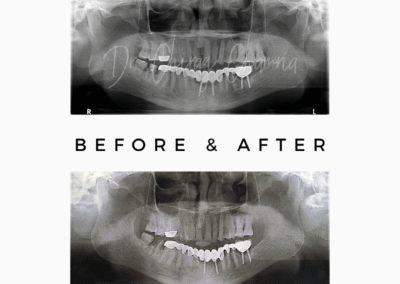

Before After Smile Makeover